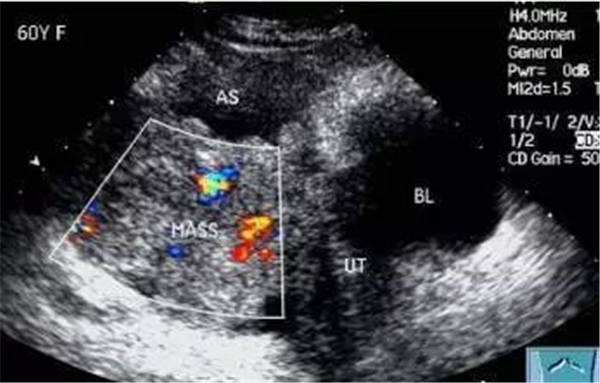

血栓

血栓是血栓性肺栓塞最典型的特征,位于右房或右室中的血栓可形態各異,而位于肺動脈內時則常表現為大塊血栓,從主干延續至一側或雙側肺動脈分支。右肺動脈主干血栓易于顯示,左肺動脈因顯示較短,血栓不易顯示。此外,需注意將血栓與右心系統腫瘤相鑒別。

右心血栓 肺動脈血栓